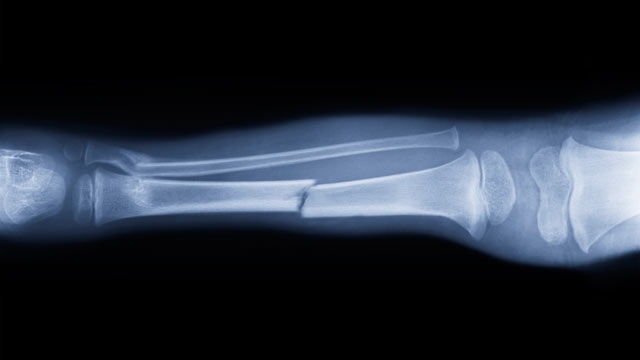

Hogyan gyógyítható a feltört láb?